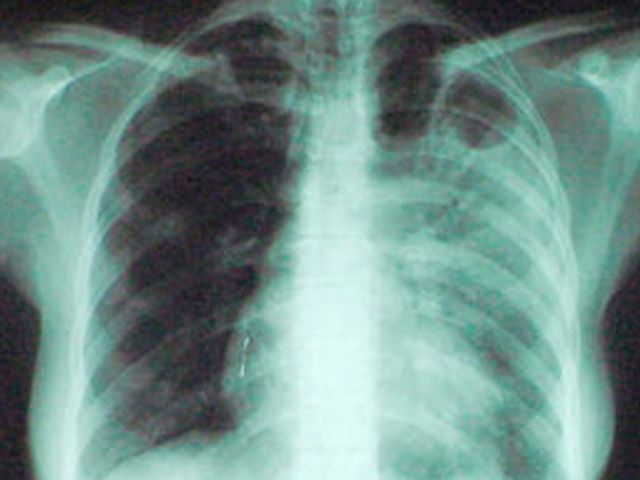

Головне управління статистики інформує, що на обліку в лікувально-профілактичних закладах області станом на кінець 2013 рокуперебували 1087 хворих на увсі форми активного туберкульозу, більшість (95,6%) з яких хворіє на активну форму туберкульозу легенів.

З уперше в житті встановленим діагнозом активного туберкульозу у 2013 році, як і у 2012-му, зареєстровано 959 осіб, або 69,5 особи у розрахунку на 100 тис. населення області. Із загальної кількості хворих, яким торік встановлено такий діагноз, 62,5% – із сільської місцевості, кожен четвертий – у віці 15–34 роки, кількість чоловіків у 2 рази більша, ніж жінок (639 проти 320).

У 2013 року від туберкульозу в області померло 153 особи, що на 3,4% більше, ніж у 2012р. і складає 0,9% від загальної кількості померлих. У сільській місцевості від цієї недуги померло майже у 2 рази більше, ніж у міських поселеннях – 101 та 53 особи відповідно. Порівняно з 2012 роком кількість померлих від туберкульозу у сільській місцевості збільшилась на 6,3% , у міських поселеннях зменшилась на 1,9%.